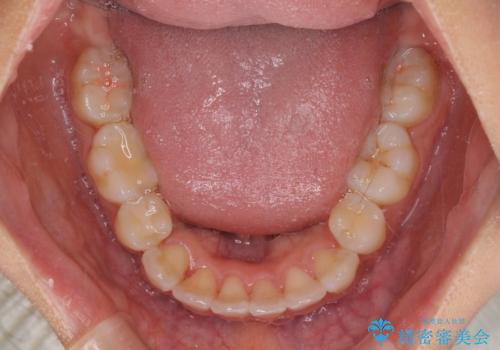

下顎の正中を上顎に合わせる処置が難航し、期間が長引きました。

最終的には上下の正中も合い、横顔の印象が変わるほどスッキリとした口元となりました。